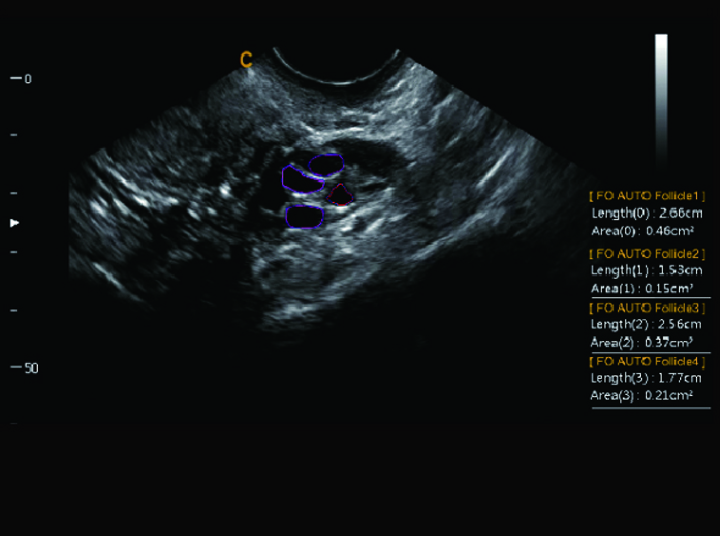

Detección de Folículos Automatica